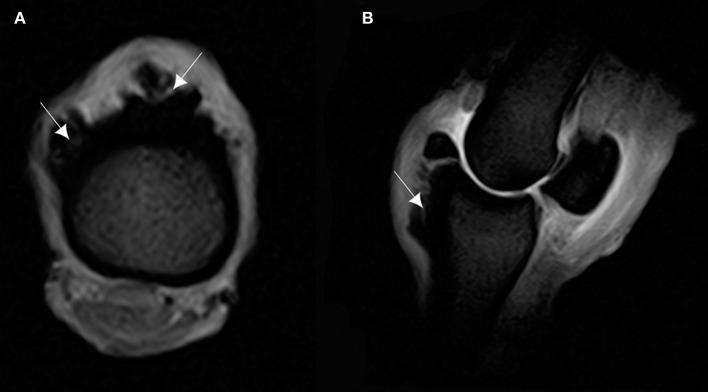

This study aimed at describing anatomo-histopathological and imaging features, using computed tomography and magnetic resonance imaging on six forelimbs of Tbourida horses, that presented a particular bone exostosis on the dorsal and proximal part of the first phalanx, diagnosed by X-ray. Gross anatomy of the bone exostosis revealed an irregular surface with poly-lobulated tissue masses showing a cauliflower shape. The diameter/depth varied from 0.5 to 5.1 cm with a mean of 3.9 ± 0.9 cm. The capsule of the metacarpophalangeal joint was hypertrophic and showed many invaginations in the inner part, in contact with the bone exostosis. Computed tomography revealed cortical and medullary continuity of the bone exostosis, with the underlying bone, and remodeling of the cortical surface of the dorsal and proximal part of the first phalanx. Magnetic resonance imaging showed an increased signal intensity of the bone exostosis on the T1- and T2-weighted gradient fast echo. Histological examination of the bone exostosis revealed a cap of hyaline cartilage, including large foci of endochondral ossification with a base of cancellous bone surrounding marrow spaces, which confirmed the diagnosis of osteochondroma. The capsule of the metacarpophalangeal joint showed a large amount of recently formed connective tissue fibers in its inner part, interspersed with mature connective tissue. The hyperextension of the metacarpophalangeal joint during a Tbourida show, which occurs on a hard ground surface, and the use of hobbles in horse stabling are most likely responsible for the outgrowth of an osteochondroma of different shapes and sizes, and fracture complications in some cases.

本研究旨在描述6匹图里达马前肢的解剖组织病理学和影像学特征,这些马的第一指骨背侧和近端出现了一种特殊的骨外生骨疣,通过X线诊断。骨外生骨疣的大体解剖显示其表面不规则,有多个分叶状组织块,呈菜花状。直径/深度在0.5至5.1厘米之间,平均为3.9±0.9厘米。掌指关节的关节囊肥厚,内部有许多内陷,与骨外生骨疣接触。计算机断层扫描显示骨外生骨疣与下方骨骼的皮质和髓质连续,第一指骨背侧和近端的皮质表面有重塑。磁共振成像显示在T1加权和T2加权梯度快速回波上骨外生骨疣的信号强度增加。骨外生骨疣的组织学检查显示有一层透明软骨帽,包括大量软骨内成骨灶,其底部为围绕骨髓腔的松质骨,这证实了骨软骨瘤的诊断。掌指关节的关节囊内部有大量新形成的结缔组织纤维,夹杂着成熟的结缔组织。图里达马表演期间在坚硬地面上发生的掌指关节过度伸展以及马厩中使用缰绳极有可能导致不同形状和大小的骨软骨瘤长出,在某些情况下还会引发骨折并发症。